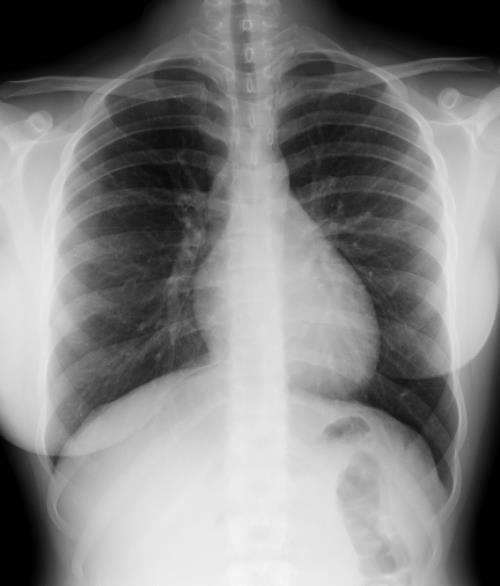

Sombra “simétrica y de densidad “uniforme” de las mamas